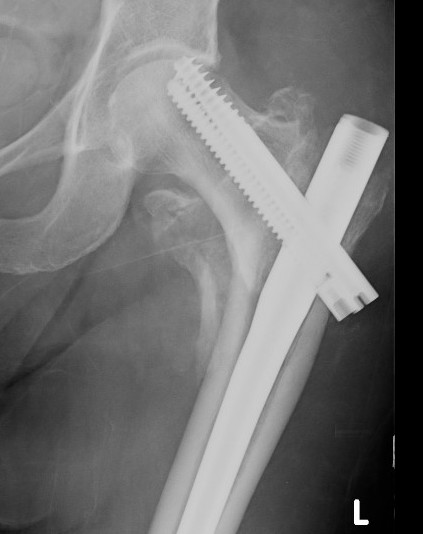

Sliding hip screw/dynamic hip screw

Dynamic hip screw

Mechanism

Plate is a lateral tension band whilst the sliding screw allows controlled fracture impaction

Technique

- traction table with anatomic reduction

- traction, adduction, internal rotation

Guide wire

- centred in femoral head in 2 planes

- tip-apex distance < 25 mm